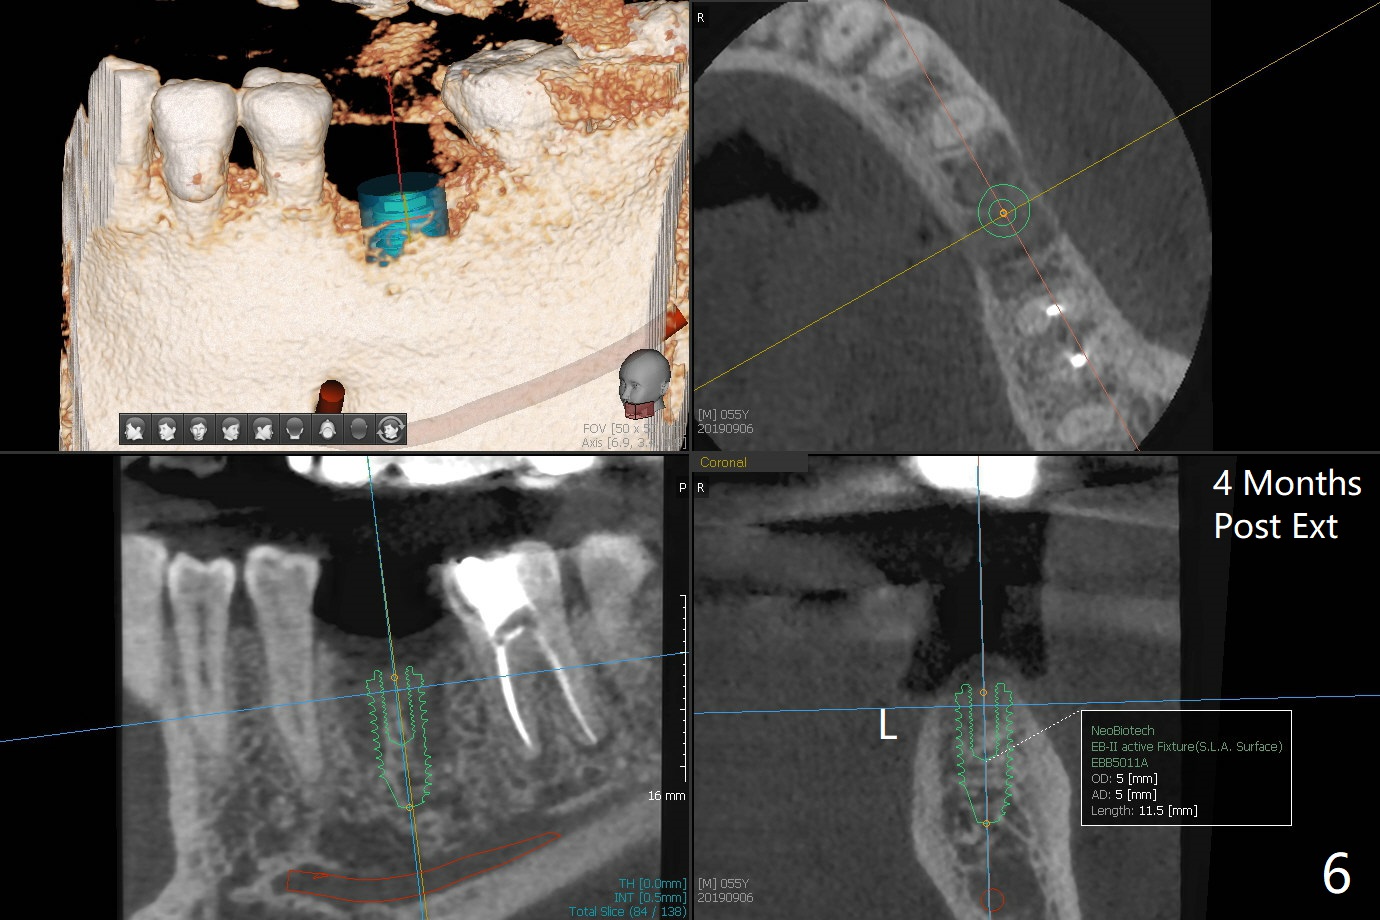

A 54-year-old man has several restoration with sign of bruxism (Fig.1). The tooth #19 has mesiodistal crack with furca radiolucency (Fig.2 *). To prevent abutment screw loosening associated with heavy mastication, a 6x17 mm tissue-level implant will be placed free hand due to the patient's tight schedule (blue, Fig.3,4,5). Pink: abutment; green: restoration which will be seated partially in the implant to reduce abutment loosening. To reduce possible neuropathy and have freedom to place implant deep, the implant length will be shorter, 14 mm, if the bone is dense. Take photos to show the crack line and buccal swelling. The patient returns for implant 4 months post extraction without bone graft in his home country with bone loss (Fig.6). In the presence of the accessory canal (Fig.7 *), a 5x10 mm implant is safe to be placed.